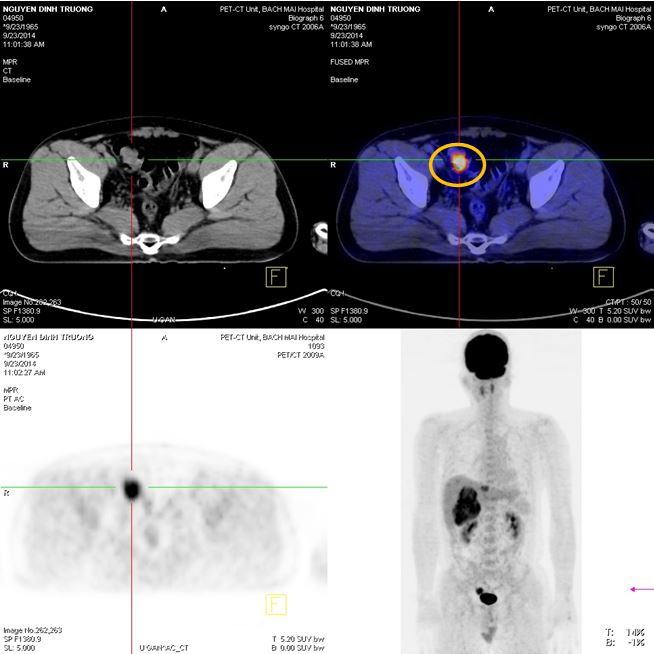

PET/CT

Hình 2: Hình ảnh khối u hạ phân thùy VI 8,6x7,0 cm, max SUV=7,49; khối u gan trái 3,0x2,0 cm, maxSUV=5,06

Hình 3: Hình ảnh khối u đại tràng 2,1 x2,6x 2,9 cm, max SUV=11,65